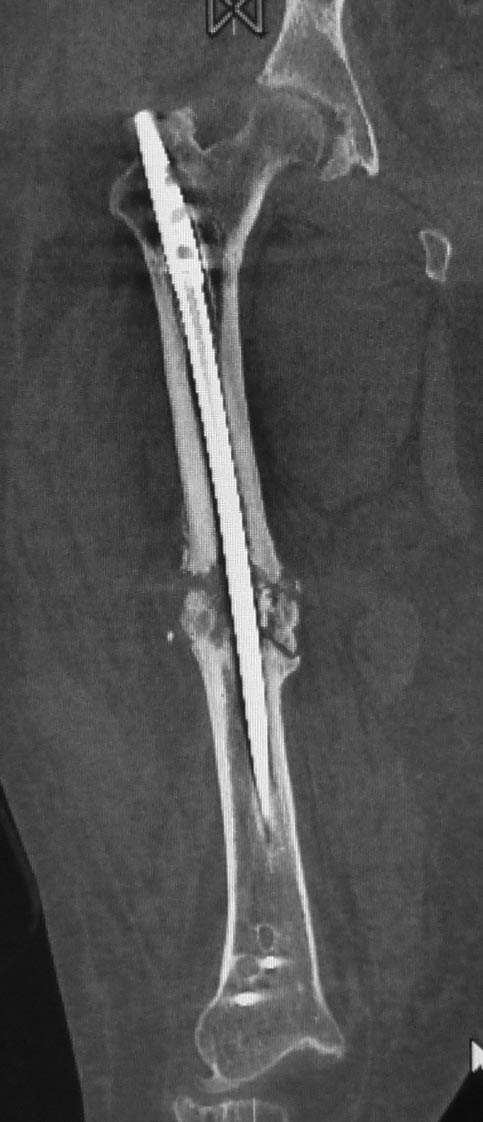

Уважаемые коллеги. Хотелось бы выслушать мнения и советы по представленному случаю. Пациент 42 лет, вес 130 кг, рост около 160 см, сахарный диабет в легкой форме (впервые выявлен после травмы). Травма в феврале 2011 г. - упал с мотоцикла на отдыхе за рубежом. По возвращении в Россию был прооперирован в несколько этапов: в марте 2011 г. - остеосинтез обеих костей правого предплечья пластинами по поводу открытого перелома; интрамедуллярный остеосинтез правого бедра; остеосинтез проксимального конца правой большеберцовой кости. В апреле 2011 г. был доставлен 1 блокирующий винт в дистальное отверстие гвоздя и выполнена пластика крестообразных и наружной боковой связок левого коленного сустава. В феврале 2012 г. были удалены фиксаторы с проксимального конца правой большеберцовой кости и выполнена пластика крестообразных и наружной боковой связок правого коленного сустава. За это время пациент смог начать ходить, сначала с костылями, а затем - без дополнительной опоры. Летом 2013 г. решил укрепить ноги с помощью подъемов пешком на пятый этаж. В результате - усталостная рефрактура правого бедра и перелом интрамедуллярного гвоздя. 09.09.2013 - реостеосинтез латеральным бедренным гвоздем с пластикой костной аутостружкой + СhronoS. Сейчас, через 6 мес после операции, может ходить без дополнительной опоры, периодически беспокоит болезненность в области правого бедра. На сегодняшних КТ - отсутствие признаков консолидации. Нужно ли что то делать и, если да, то что? Рассматриваемые варианты: повторная костная пластика дефекта; доставить блокирующие винты (самый проксимальный винт был удален через 3 мес после операции). Еще раз менять гвоздь не хотелось бы. На представленных снимках: бедро в 2011 г., через несколько мес после операции; в 2012 г., на стадии консолидации; со сломанным гвоздем; сразу после повторной операции (3 рентгенограммы). Все КТ - сегодняшние. Заранее спасибо за ответы.

Сергей, а ?ожно по подрбнее о костной пластике при в сентябре 2013 приреостеосинтезе. Что это была за пластика? доступ? было ли рассверливание? диаметр гвоздя?

Источник проблем - отсуствие рассверливания, тонкий гвоздь и костная пластика. При интрамедуллярном остеосинтезе (относительная стабильность) класть кусочки кости открыто бесполезно - не приживут. Только еще ухудшили кровоснабжение концов. А что там с длиной сегмента? Если длина не потерялась - реостеосинтез с рассверливанием, как А.Семенистый написал. Если укорочение - удалить, остеотомия на другом уровне и дистракиця, на стыке - компрессия, и по достижении нужной длины - заштифтовать с рассверливанием, аппарат снять только после запирания гвоздя.

Костная пластика делалась стружкой из фрагментов большого вертела: верхний конец предыдущего гвоздя был погружен в него на пару см (первый гвоздь ставился не у нас, я только доставил второй дистальный блокирующий винт)и гранулами СhronОs. Учитывая совершенно необъятные размеры бедра, удаление сломанного гвоздя получилось достаточно травматичным. Пришлось широко открываться проксимально, на уровне перелома и дистальнее, чтобы сформировать окошко для выбивания дистального отломка гвоздя (дистальный конец гвоздя не имел отверстия). После операции около месяца собиралась жидкость в области большого вертела (серома), на фоне пункций постепенно ушла. Поэтому и хотелось бы избежать еще одного вмешательства на уровне большого вертела.

При сопутствующей травме грудной клетки или при политравме допускается фиксация тонкими гвоздями с минимальным или без рассверливания канала. Тактика уменьшает second hit при damage control и стабилизирует перелом временно, но не гарантирует сращение. Рассверливание канала, кроме стабильности, создает экзотермическую температуру, которая улучшает ангиогенез за пределы канала, и поэтому происходит образование эндооссальной консолидации.

А открытая операция на диафизе приведет к ухудшению без того нарушенного кровоснабжения и не костная стружка, а широкий хирургический доступ приводит к нарушению кровоснабжения. При следующих процедурах желательно сохранить преимущество интактного кровобращения!!

Боли в области ложного сустава подтверждают, что ожидания не помогут и приведут к повторному перелому интрамедуллярного гвоздя. Стандартная процедура - рассверливание и толстый гвоздь в динамике. Нагрузка с первых дней.